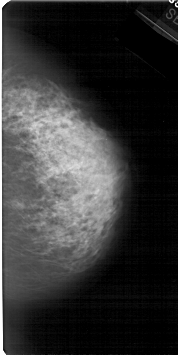

A_1531_1.LEFT_MLO

LEFT_MLO LINES 5491 PIXELS_PER_LINE 2866 BITS_PER_PIXEL 12 RESOLUTION 43.5 OVERLAY

FILE: A_1531_1.LEFT_MLO.OVERLAY

TOTAL_ABNORMALITIES 1

ABNORMALITY 1

LESION_TYPE CALCIFICATION TYPE PLEOMORPHIC DISTRIBUTION CLUSTERED

ASSESSMENT 4

SUBTLETY 4

PATHOLOGY MALIGNANT

TOTAL_OUTLINES 1

BOUNDARY